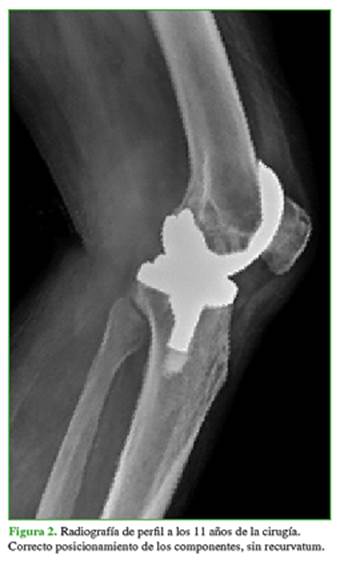

Hombre de 77 años, con antecedentes clínicos de obesidad, diabetes, insuficiencia renal crónica, hipertensión arterial, insuficiencia cardíaca, pie de Charcot bilateral y marcapasos por un bloqueo de la conducción cardíaca. Había sido sometido a un reemplazo total de rodilla izquierda por genu varo artrósico, en noviembre de 2006. En esa oportunidad, se le colocó una prótesis estabilizada a posterior (Scorpio®, Stryker, NJ, EE.UU.) y tuvo una buena evolución durante casi 12 años (Figuras 1 y 2).

En octubre de 2018, consulta por dolor e inestabilidad de rodilla en recurvatum que le imposibilita la marcha. En el examen físico, se observó una rodilla estable al varo-valgo, con movilidad pasiva de 0-100º y movilidad activa de 10-100º, y una clara debilidad en la fuerza muscular del cuádriceps.

En las radiografías de frente, se visualizó un implante en posición y alineación correctas, sin signos de demarcación. En las imágenes de perfil, se pudo comprobar el recurvatum de aproximadamente 20° (Figuras 3 y 4).